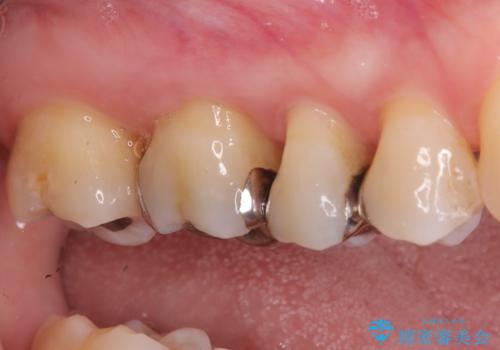

- 左上奥歯に入っている金属の詰め物(メタルインレー)の見た目を改善したいという主訴でご来院されました。お口の中の金属をなくしたいという患者様のご希望を踏まえ、天然歯に近い色と質感を持つセラミックインレーに交換する治療計画を立案。これにより、見た目の改善だけでなく、金属アレルギーのリスクを排除したメタルフリーの環境を実現することを目指しました。

治療では、まず古い金属のインレーを慎重に取り外しました。金属の下に隠れていた虫歯の再発がないかを確認し、歯を丁寧に形成。その後、精密な型取りから患者様の歯の色に合わせたオーダーメイドのセラミックインレーを作製しました。セラミックは、自然な光の透過性を持つため、周囲の歯と区別がつかないほどの美しい仕上がりとなります。適合性の高いセラミックインレーを装着することで、再発のリスクを抑えつつ、長年のコンプレックスだった銀歯がなくなり、笑顔でも気にならない自然な奥歯を取り戻していただけました。